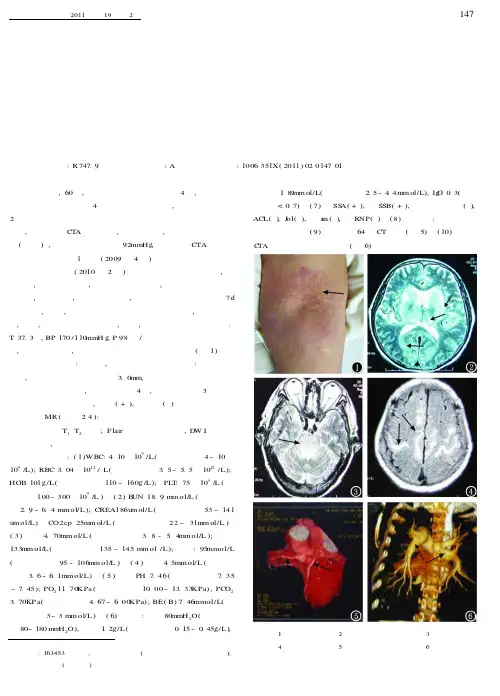

心、肺、腹查体未见异常,双下肢无浮肿,双上肢肘关节屈侧可见对称皮疹(图1)。

头颅MR (如图24):双侧皮质下白质、基底节区及丘脑、脑干对称性长T 1、T 2信号;F lair 相应区域高信号,D W I 相应区域未见异常,无强化。